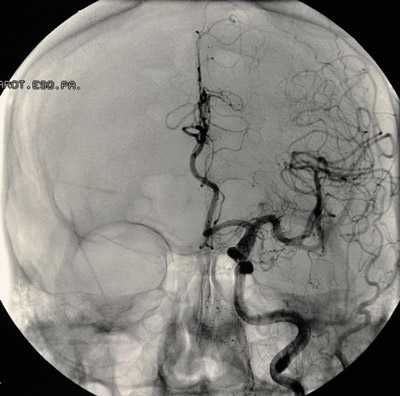

аневризма сосудов мозга на снимке

Перед планированием операции больной подвергается всевозможным обследованиям, включая анализы крови, мочи, коагулограмму, кардиограмму и т. д., как и при других оперативных вмешательствах. Для локализации и уточнения характера сосудистого образования проводят КТ, МРТ с контрастированием, ангиографию, ультразвуковое исследование с допплером.

Операция на аневризме сосудов головного мозга показана, если у пациента обнаружено аневризматическое выпячивание, размером более 7-10 мм, подтвержденное инструментальными методами диагностики:

- Ультразуковым исследованием сосудов головного мозга,

- МРТ и/или КТ головного мозга, в том числе с использованием рентгеноконтрастного вещества, введенного в сосудистое русло пациента,

- Спинномозговой пункцией с исследованием ликвора (спинномозговой жидкости) на предмет субарахноидального кровоизлиянияпри разорвавшейся аневризме.

При эндоваскулярном вмешательстве доступ к аневризме осуществляется путем пункции бедренной артерии и ведения зонда под МРТ-контролем к месту операции. На конце зонда располагается баллон, вводимый в просвет аневризмы. После того, как баллон установлен и зафиксирован в аневризме, происходит эмболизация («закупорка») аневризмы, и она становится функционально неактивной.

эндоваскулярная эмболизация аневризмы

Все этапы операции осуществляются под строгим МРТ или КТ-контролем. После вмешательства пациент около пяти суток находится в отделении реанимации, после чего может быть переведен в отделение нейрохирургии.

Весь ход эндоваскулярной операции отслеживается врачами на цифровом ангиографе, в некоторых случаях для этой цели используют томографы (КТ или МР). В качестве контрастного вещества задействуют препараты, содержащие йод. Одним из неоспоримых преимуществ метода является применение местной анестезии, что важно для пожилых и ослабленных лиц, для которых невозможно осуществить клипирование, поскольку это представляет определенную угрозу для жизни.